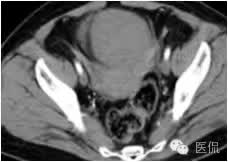

右侧卵巢肿瘤大小8*10*12cm,与膀胱后壁腹膜、盆腔侧腹膜、部分大网膜、乙状结肠直肠浆膜层前粘连,表面呈褐色坏死状,肿瘤蒂部顺时针扭转两圈,左侧卵巢正常。

◆为单发肿瘤,表现为盆腔内实性肿块,囊性区较小;境界较清楚;肿瘤体积一般较大

◆CT表现:平扫呈等或稍低密度肿块,低于子宫肌层,可伴少量低密度囊变区,无壁结节

◆增强肿瘤实性成分呈轻-中度不均匀延迟强化,明显弱于子宫肌层;也可无强化